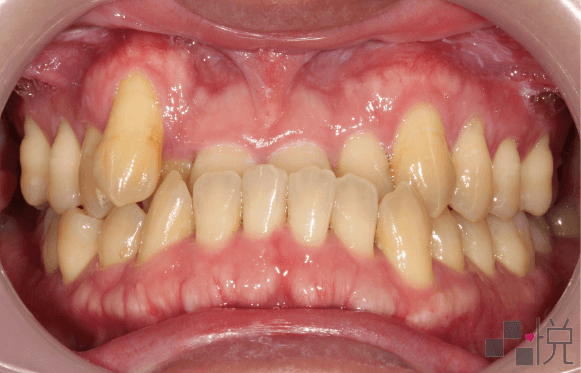

本案例治療前有輕微的「骨性戽斗」,齒列擁擠,上顎及下顎中線偏差,合併有前牙和後牙錯咬,而後牙錯咬造成了咬合干擾,使得下顎往右側歪斜。

採用不拔牙的矯正治療,並且讓下顎順時針旋轉改善戽斗的外觀。牙齒矯正後咬合干擾消失,同時改善臉部歪斜。